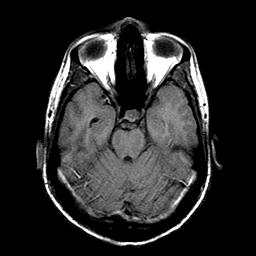

Sarcoma, MR Study #1 mr-t1 -- Slice #7

[Home][Help][Clinical] Slice 7